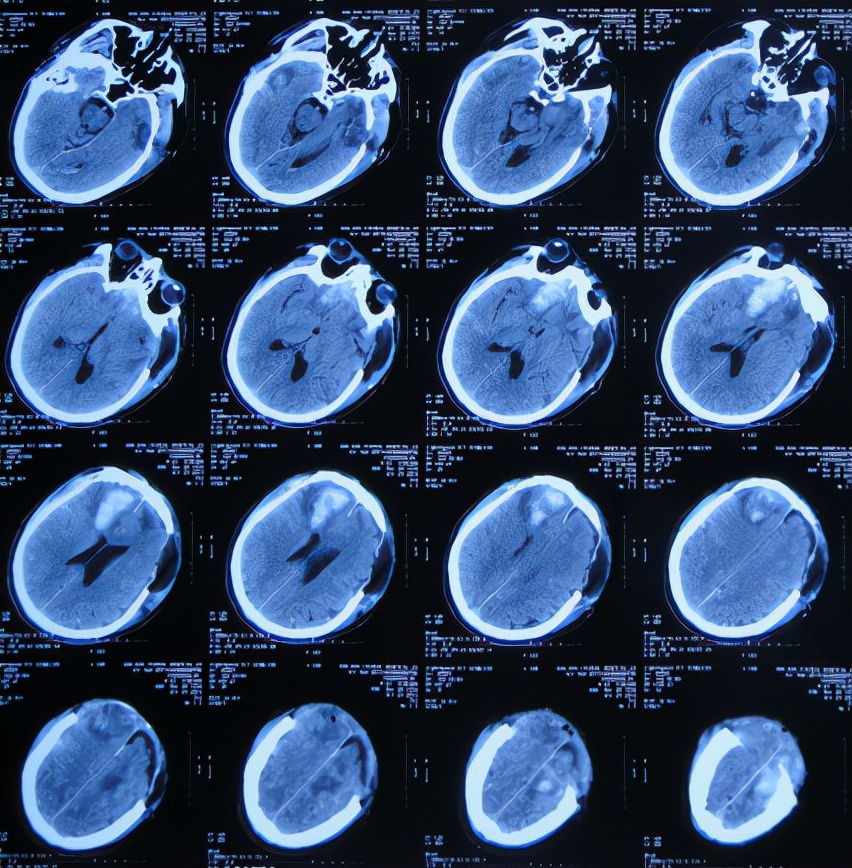

2019年10月20日患者骑电动车在马路上行驶时被大货车撞倒,当时意识清楚,只感到有些头晕,未在意就自行回家,但回家后约3-4小时出现头晕加重,并伴有恶心呕吐的症状,家人急送到当地的河北省邯郸市某医院,查头颅CT示脑出血( 图-1 );既往病史2015年曾因头部外伤致硬膜下血肿,进行了钻孔引流术。

图-1: 2019年10月20日头颅CT

急诊进行了开颅去骨瓣血肿清除术,术后次日查头颅CT示去骨瓣术后( 图-2 )。

图-2: 2019年10月21日头颅CT

开颅术后第2天即2019年10月22日,仍昏迷,查头颅CT示积血未见减少( 图-3 ),给予腰椎穿刺术。

图-3: 2019年10月22日头颅CT

开颅术后第4天即2019年10月24日,查头颅CT示积血仍未明显减少( 图-4 )。

图-4: 2019年10月24日头颅CT